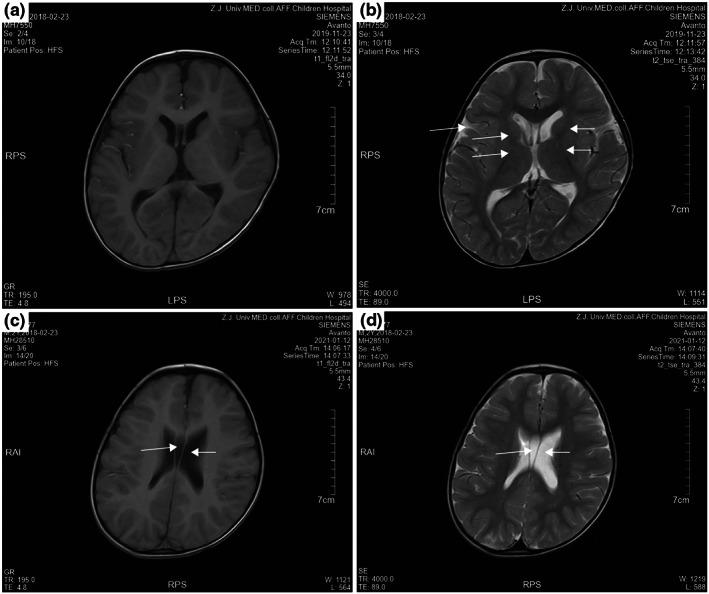

We reported a male patient with developmental delay and cerebral palsy who carried the BCL11B variant. The detailed clinical features, such as brain structure and immune detection, were described and reviewed in comparison to previous patients.

我们报告了一名携带 BCL11B 变异的男性患者,该患者患有发育迟缓伴脑瘫。详细的临床特征,如大脑结构和免疫检测,与之前的患者进行了描述和比较。